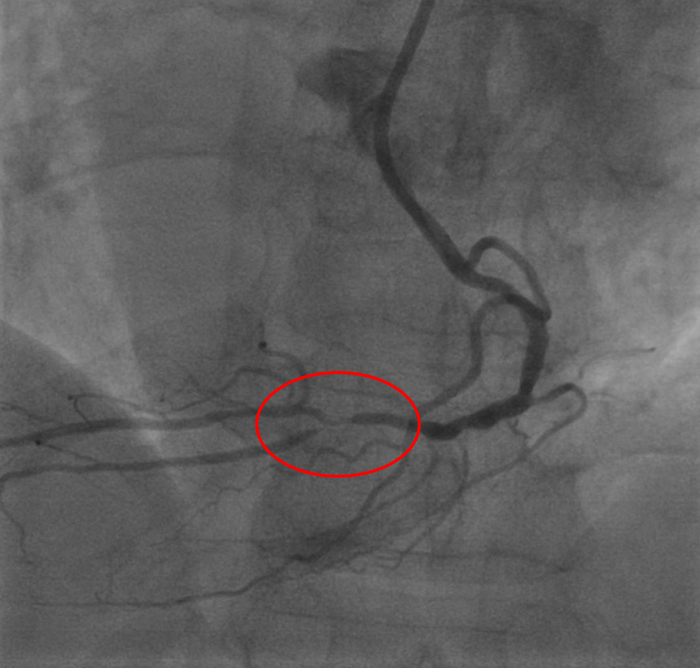

С учетом данных ВСУЗИ проводится сразу прямое (без предварительной предилатации баллоном) стентирование ПМЖА с покрытием ствола левой коронарной артерии.

Получаем такой результат

Контроль ультразвуком:

Клинически тоже все хорошо, на следующие сутки переведена в отделение. Готовится к выписке.